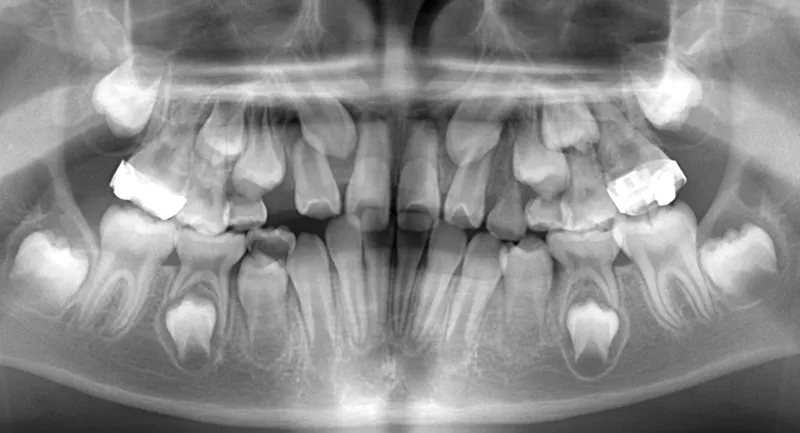

診断名 埋伏歯・反対咬合・叢生 装置名

レントゲンを撮ってみると犬歯の萌出方向がずれていました。

先ずは萌出スペースを確保してから開窓術を行い、犬歯を正しい方向へ誘導しました。